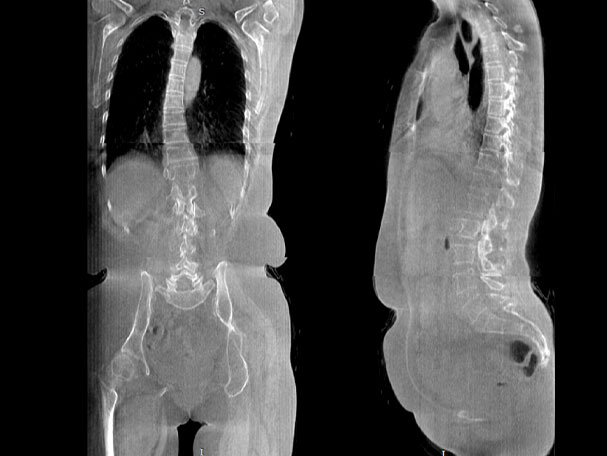

· 補位CT,提供負重位三維影像

· 引領普放走向三維精準診斷時代

填補常規CT/MR空白

助力術前規劃和術后評估

VR體繪制重建

氣道三維影像重建